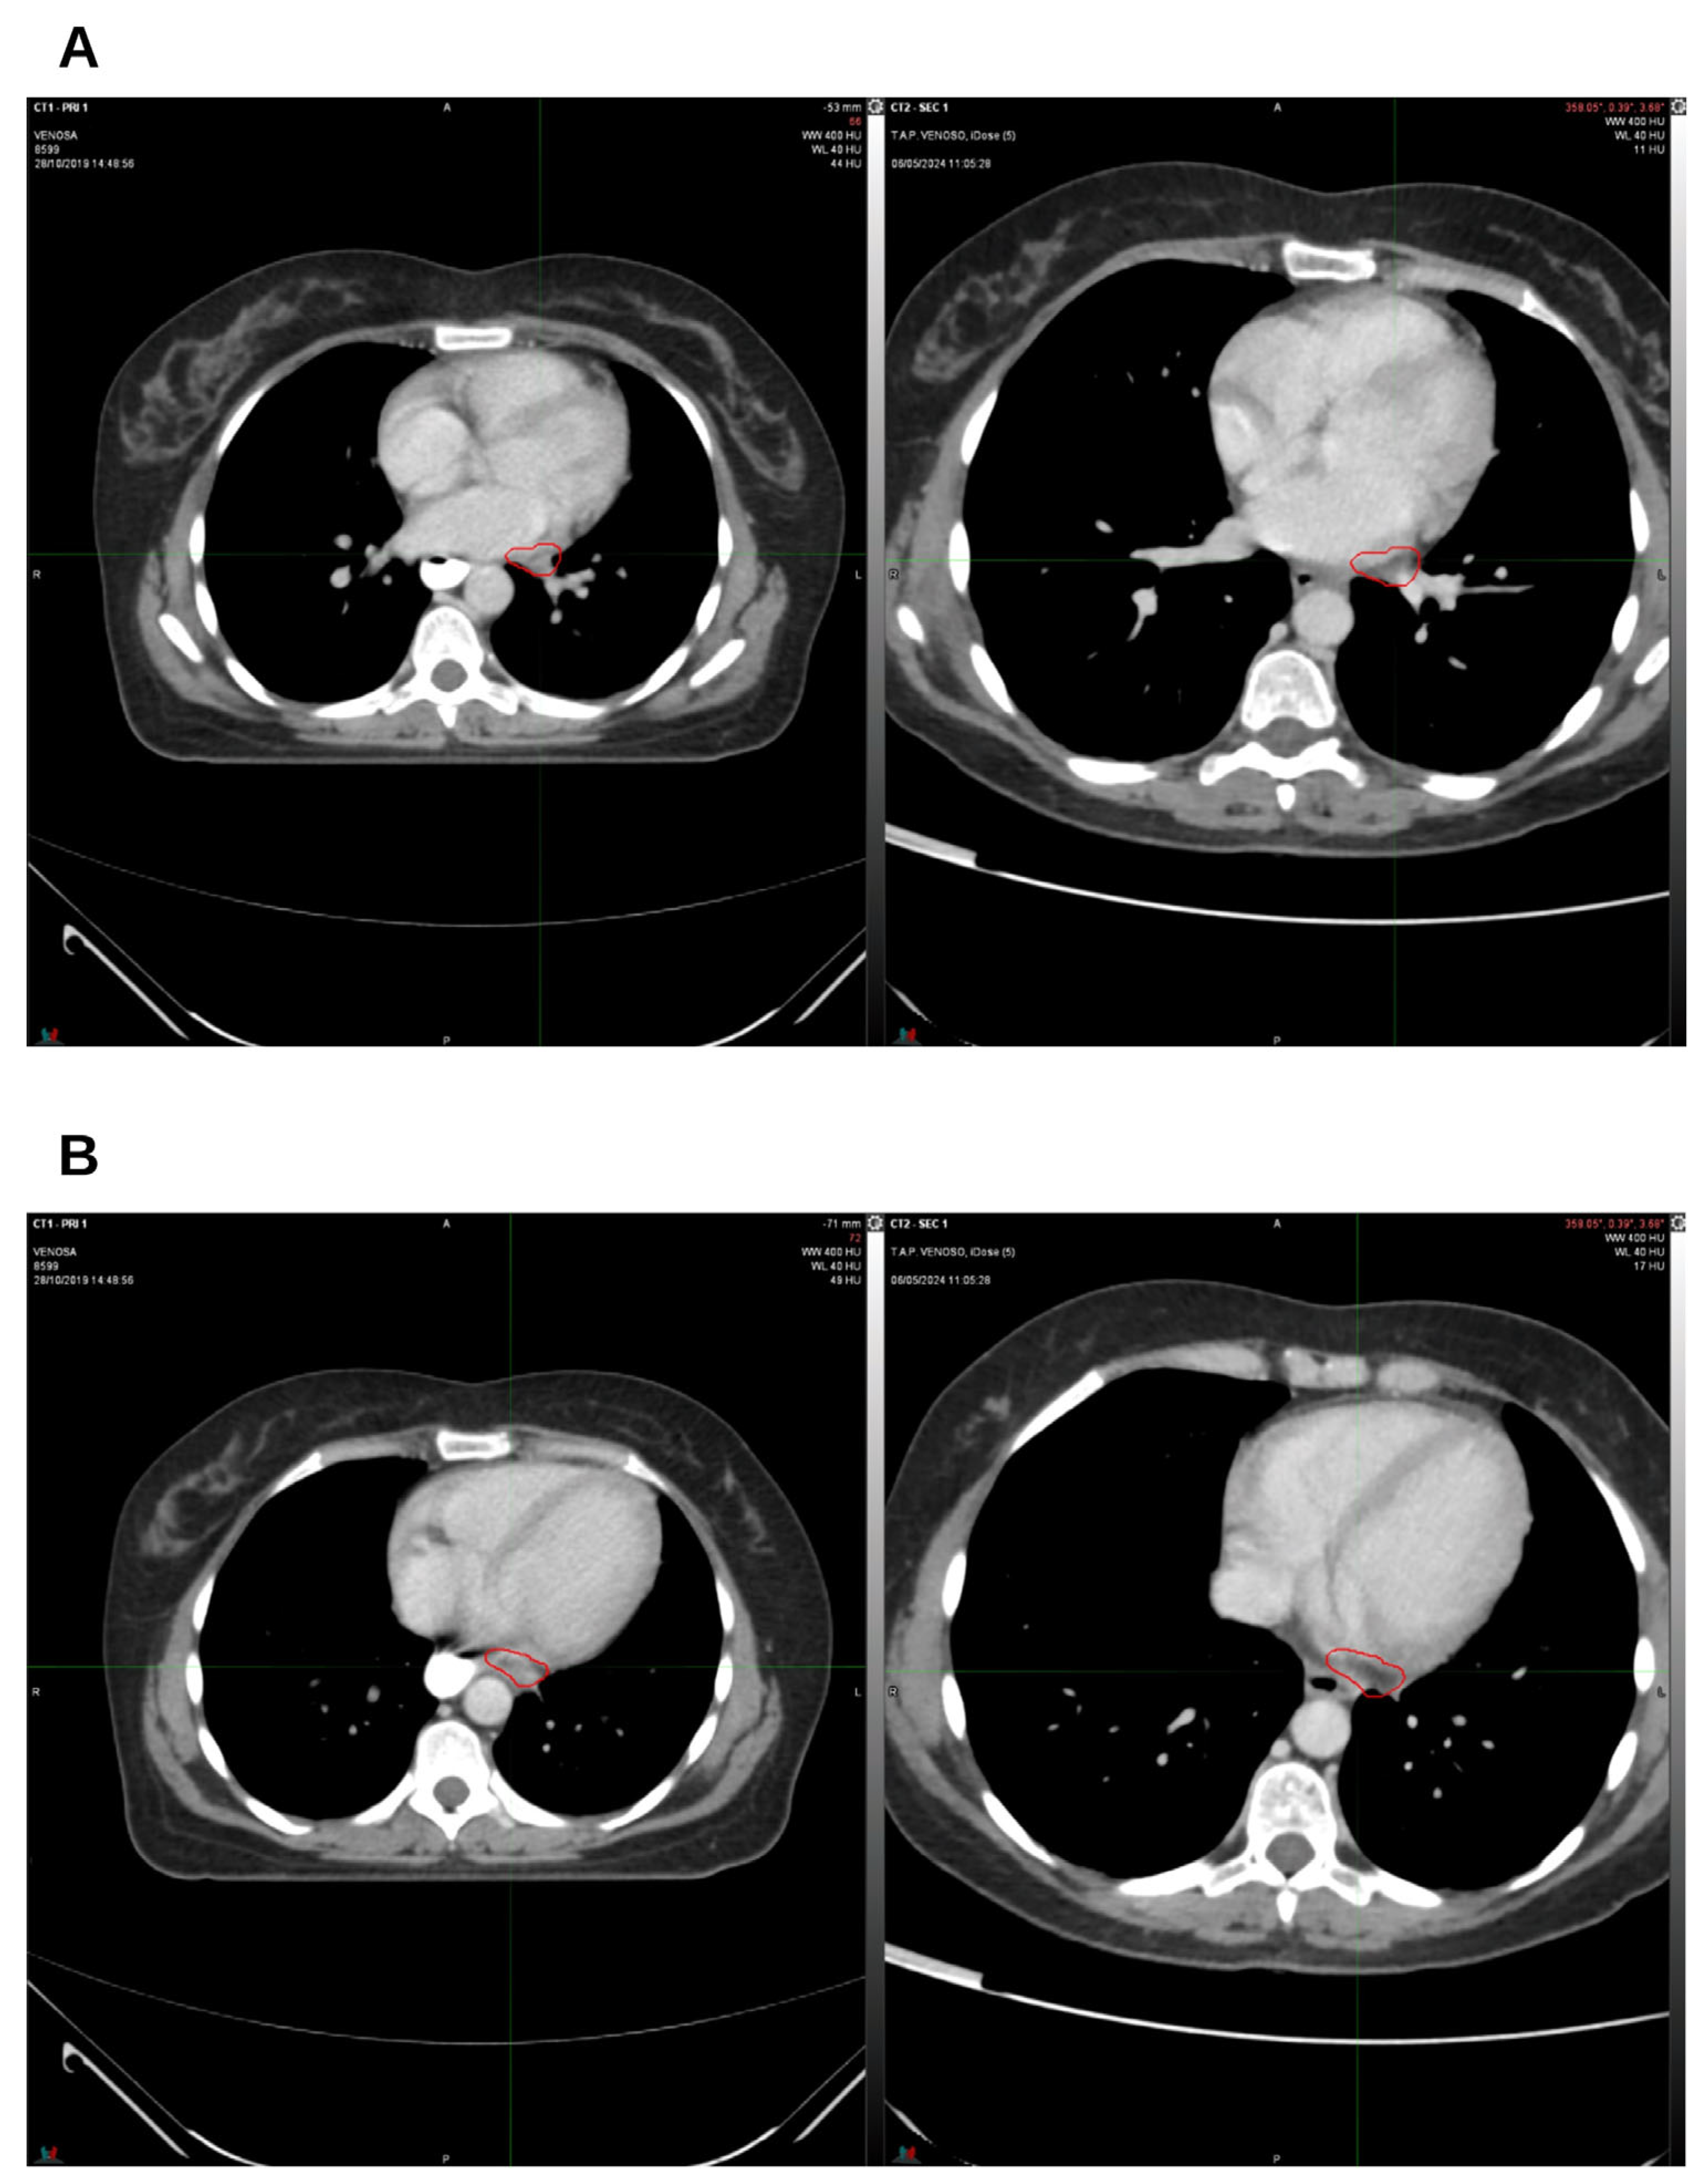

2. Case Presentation